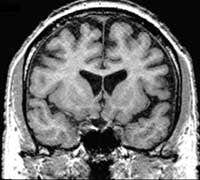

Sharma’s team used magnetic resonance imaging (MRI) to scan the brains of 37 people experiencing their first hallucinations and 31 healthy people.

The scans showed significant differences between the brains of the two sets of subjects. Sharma concludes that the brain changes began some time before the schizophrenic patients first suffered a psychotic episode.

He found that the brains of the schizophrenic patients were smaller than normal. They also had abnormal temporal lobes – a part of the brain linked with speech and the experience of hallucinations.